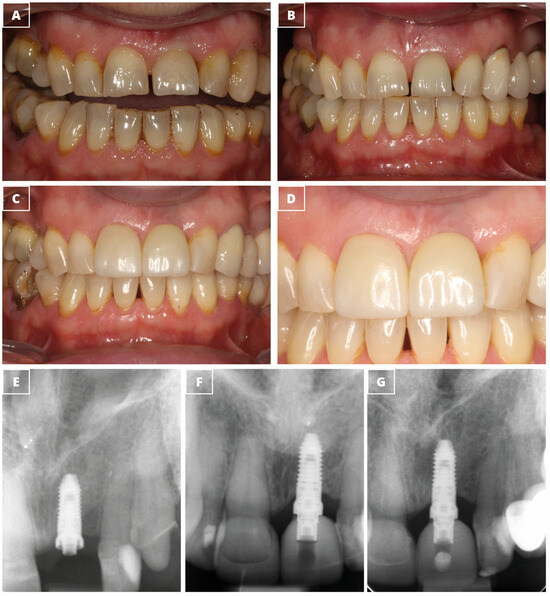

Retrospective Study of Functional and Esthetic Outcomes Using Narrow-Diameter Implants for Single Upper Central Incisor Replacements

3. Results